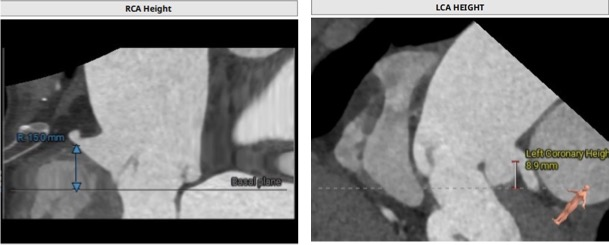

左侧冠脉开口高度低,LCA 8.9mm,左瓣叶长度11.1mm;右侧冠脉开口高度可,RCA 15.0mm:

主动脉瓣环夹角42°: